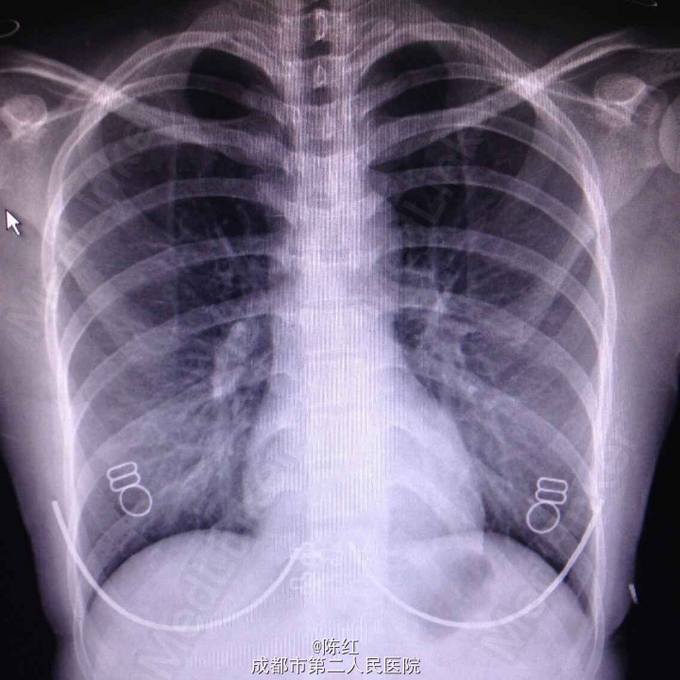

入院T37.49℃,P110次/分,R20次/分,BP108/70mmHg。神清,急性病容,皮肤黏膜未见黄染,全身无皮疹,双侧扁桃体Ⅱ度肿大,可见较多白色分泌物,颈部、双侧腹股沟可扪及数个肿大淋巴结,质软,活动,约1cm左右。双肺呼吸音清,未闻及干湿鸣,心律齐,未闻及心脏杂音,腹软,无压痛,双下肢无水肿。入院胸片未见异常。腹部彩超:脾脏稍长大。颈部彩超:双侧颈部淋巴结长大,咽拭子提示正常菌群生长,无真菌生长。痰培养正常菌群生长。EB病毒Ig M 109U/ml,Ig G 100U/ml,血常规:WBC13.29×10^9/L,N5.6%,L80.2%,异常淋巴细胞15%。生化:ALT 218U/L,AST 185U/L,心电图、心脏彩超、泌尿系+妇科彩超、输血前十项、免疫全套、肾功、电解质、血脂、血糖、血沉、PCT、凝血三项+D二聚体、大小便常规无明显异常。